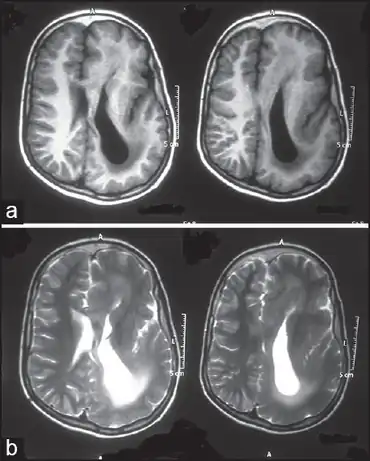

| Linear nevus sebaceous syndrome-(a)Left hemimegalencephaly with agyria-pachygyria complex b)left ventricle colpocephaly | |

The major neurological abnormalities include mental retardation to varying extent, seizures, and hemiparesis.[7] Seizures, when present, typically begin during the first year of life.[8] The most common structural central nervous system abnormalities in Schimmelpenning syndrome are hemimegalencephaly and ipselateral gyral malformations.[3]